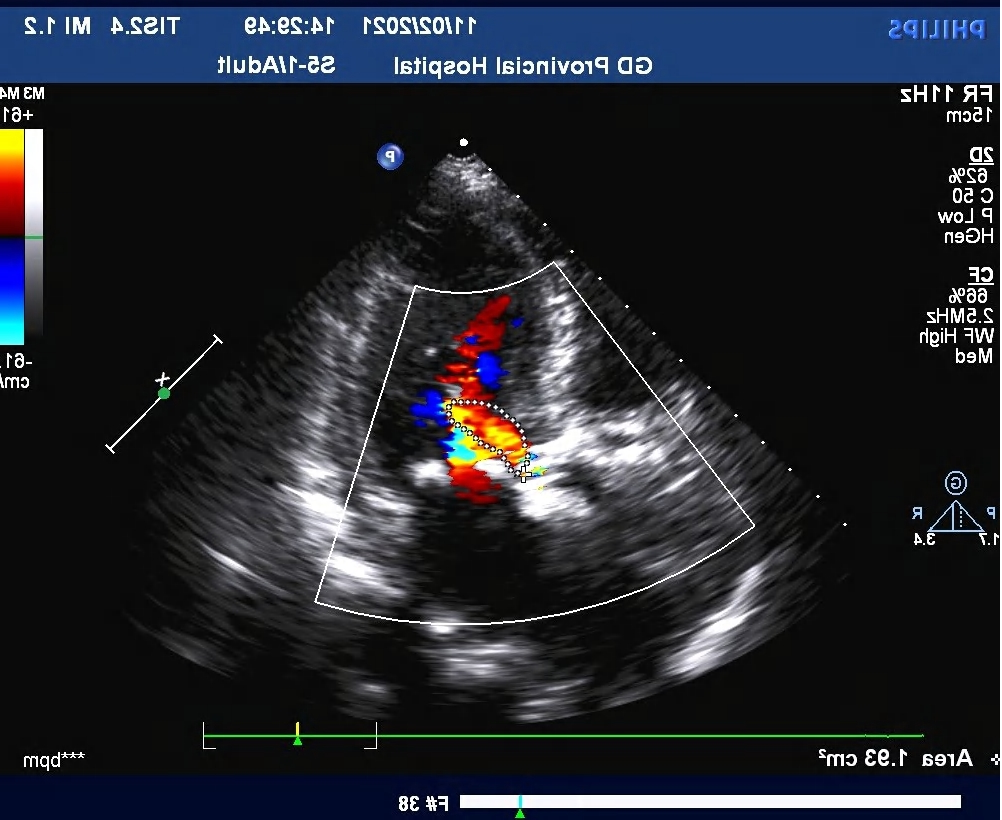

术后超声

三尖瓣反流,彩束面积 1.5cm²,估测肺动脉收缩压 24mmHg。